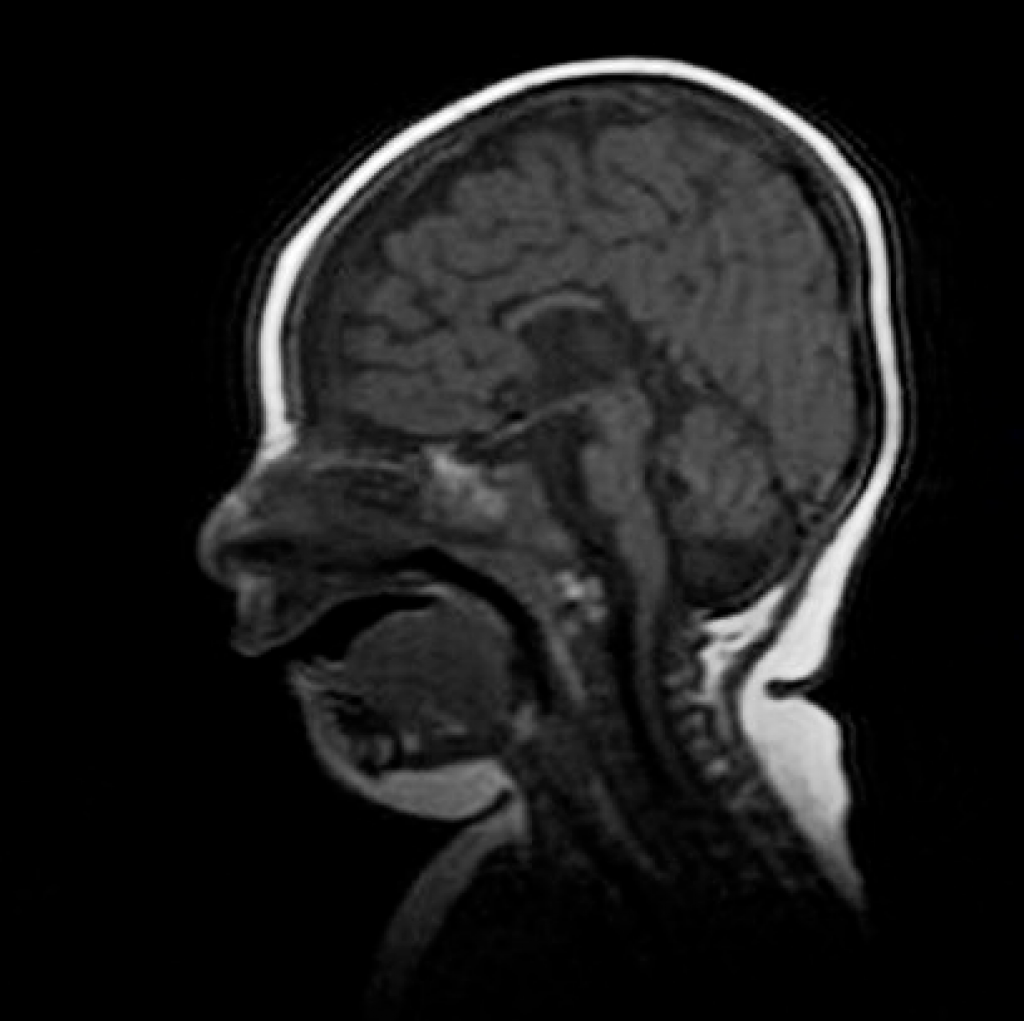

МРТ снимки мальформации Денди-Уокера